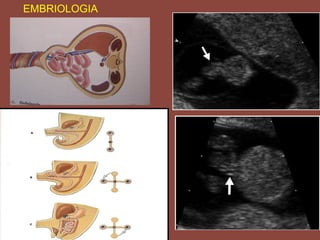

EMBRIOLOGIA